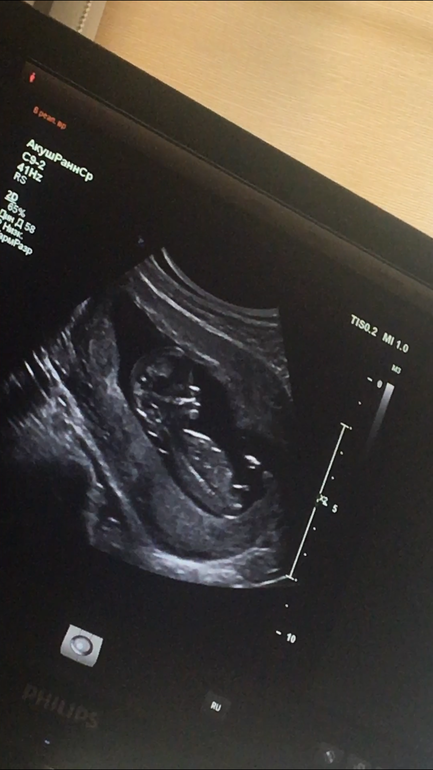

Наш первый скрининг 😍❤️ И пол крохи 😏

Результаты: УЗИ, КТГ, доплера, скринингаВот и прошли мы первый скрининг 😍 страха было..полные штаны 😂😂 но все просто идеально 😍🙏 врач раза три повторил что у меня и у ребёнка все хорошо 😂😂как будто понимал,что мне не верится 😂

теперь вопросик к вам девчонки,кто шарит в УЗИ и может распознать пол 😏 врач конечно же сам заговорил на эту тему,потому что не смотря на маленький срок он почти со стапроцентной уверенностью сказал пол 🙈 но я хочу у вас поинтересоваться))правда на столько видно?и кто же в теремочке живёт?😍